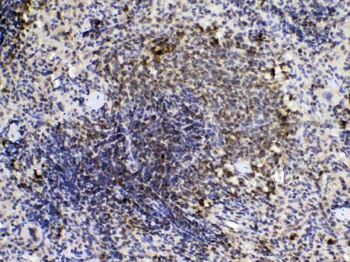

10 μg, 100 μgCYPA Rabbit Polyclonal Antibody [orb100498]

FC, IF, IHC-Fr, IHC-P, WB

Bovine, Canine, Porcine, Rabbit

Human, Mouse, Rat

Rabbit

Polyclonal

Unconjugated

50 μl, 100 μl, 200 μlFKBP52 Antibody: APC [orb147210]